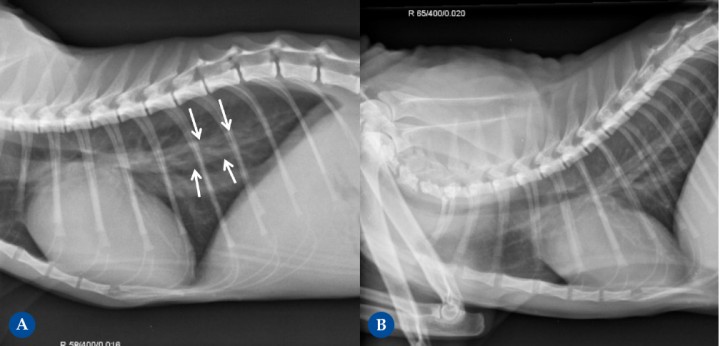

<p>Perro mestizo macho castrado de 12 años presentado para la investigación de soplo cardíaco debido a enfermedad degenerativa de la válvula mitral. La radiografía de la Fig. 4A (proyección lateral derecha) muestra cardiomegalia evidente, con un aumento severo del cuadrante caudodorsal, correspondiente con la dilatación marcada del atrio izquierdo (flechas negras). Esta causa elevación de la tráquea (paralela a la columna vertebral, cabezas de flecha negra) con compresión bronquial (puntos negros) debido al aumento de tamaño del atrio izquierdo. Ambos ventrículos están incrementados de tamaño, resultando en una silueta cardíaca que ocupa aproximadamente 3,5 espacios intercostales (ref<2,5-3). La presencia de leve patrón intersticial dorsocaudal hace sospechar de fases iniciales de insuficiencia cardíaca congestiva izquierda. La radiografía de la Fig. 4B (proyección lateral derecha) corresponde al mismo paciente, mostrando progresión severa de la enfermedad, ahora en fase terminal. Muestra marcada cardiomegalia generalizada, con la silueta cardíaca ocupando unos 4 EIC, con marcado desplazamiento dorsal de la tráquea y con compresión de los bronquios. También se detecta un patrón pulmonar intersticial generalizado con áreas de marcado aumento de la opacidad pulmonar (patrón alveolar), correspondiente a edema pulmonar cardiogénico marcado, signo de insuficiencia cardíaca izquierda.</p>

Perro mestizo macho castrado de 12 años presentado para la investigación de soplo cardíaco debido a enfermedad degenerativa de la válvula mitral. La radiografía de la Fig. 4A (proyección lateral derecha) muestra cardiomegalia evidente, con un aumento severo del cuadrante caudodorsal, correspondiente con la dilatación marcada del atrio izquierdo (flechas negras). Esta causa elevación de la tráquea (paralela a la columna vertebral, cabezas de flecha negra) con compresión bronquial (puntos negros) debido al aumento de tamaño del atrio izquierdo. Ambos ventrículos están incrementados de tamaño, resultando en una silueta cardíaca que ocupa aproximadamente 3,5 espacios intercostales (ref<2,5-3). La presencia de leve patrón intersticial dorsocaudal hace sospechar de fases iniciales de insuficiencia cardíaca congestiva izquierda. La radiografía de la Fig. 4B (proyección lateral derecha) corresponde al mismo paciente, mostrando progresión severa de la enfermedad, ahora en fase terminal. Muestra marcada cardiomegalia generalizada, con la silueta cardíaca ocupando unos 4 EIC, con marcado desplazamiento dorsal de la tráquea y con compresión de los bronquios. También se detecta un patrón pulmonar intersticial generalizado con áreas de marcado aumento de la opacidad pulmonar (patrón alveolar), correspondiente a edema pulmonar cardiogénico marcado, signo de insuficiencia cardíaca izquierda.